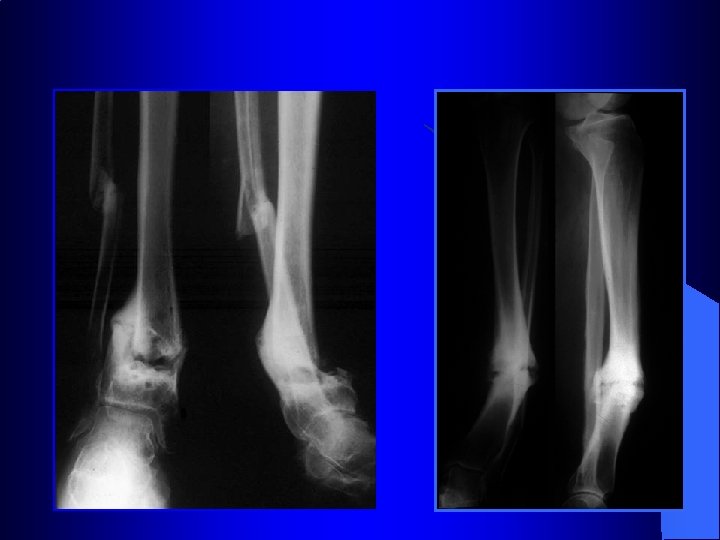

Synthèse des fractures des malléoles

Traitement des fractures malléolaires 54 ans Bon résultat à 61